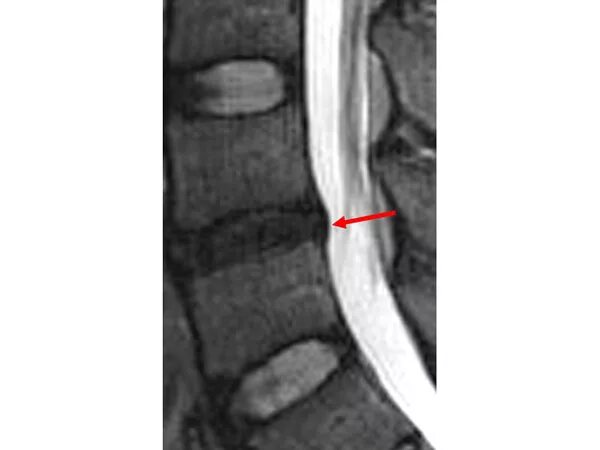

Грыжи дисков с3 с7